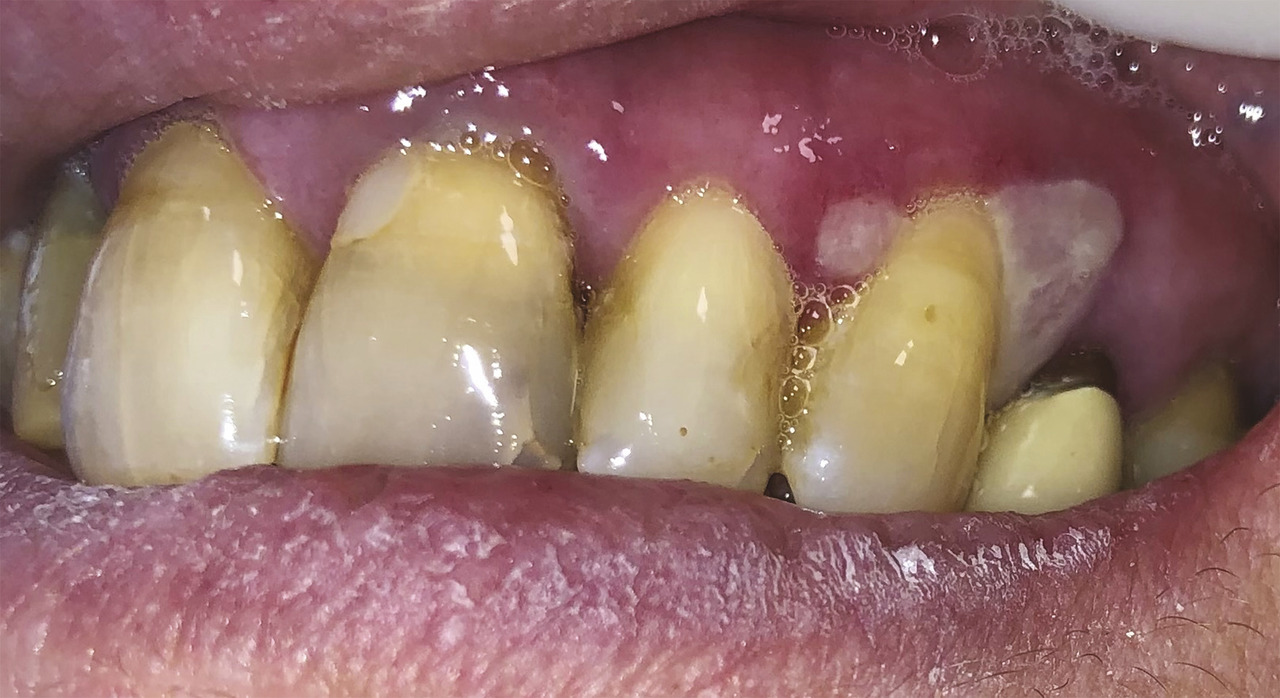

Une patiente de 61 ans consulte pour une gingivorragie diffuse persistante et douloureuse, ainsi que des ulcérations buccales récurrentes au cours des trois derniers mois. Ses antécédents médicaux comprennent une thyroïdectomie substituée par une hormonothérapie et un reflux gastro-œsophagien. On note l’absence d’intoxication alcoolo-tabagique. La patiente ne rapporte pas de modification récente de ses traitements, de son alimentation, de son dentifrice ou de ses habitudes de vie, ni de symptôme extra-oral. Malgré l’éviction des aliments acides tels que le citron ou le vinaigre, ses symptômes persistent. L’examen endobuccal révèle des lésions gingivales hyperkératosiques et érythémateuses, une lésion bulleuse gingivale (fig. 1 ) et plusieurs érosions (fig. 2 ) associées à une gingivite légère. Le signe de Nikolsky est positif, correspondant à l’érosion induite par un frottement sur une peau ou une muqueuse d’apparence saine, suggérant une maladie bulleuse. Aucune adénopathie cervicofaciale n’est objectivée lors de l’examen clinique.